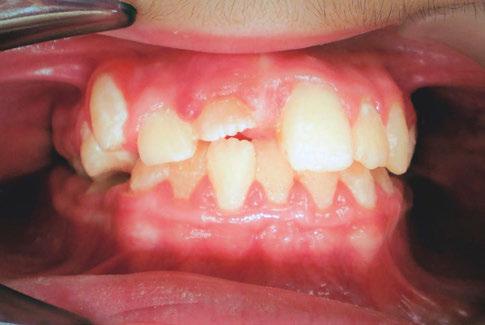

At the postoperative consultation with the mother, we told her the tooth’s complete root formation might prevent its eruption. Orthodontic extrusion of the incisor was ruled out due to his behavior. A conservative approach with observation only was elected as treatment modality. This patient returned for follow-up appointments at ages 10, 11, 12, and 13. During all these visits, the maxillary right permanent central incisor had not erupted. At age 14, due to recurrent dental caries, the patient was taken to the local children’s hospital for dental rehabilitation again. During this second hospitalization, we noticed that the right maxillary central incisor was partially erupted into the oral cavity (Figure 4).

Figure 4: Photograph of area at 14 years old during second rehabilitation under general anesthesia